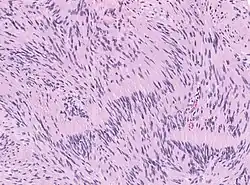

Die Therapie besteht in der chirurgischen Entfernung (Resektion) oder Bestrahlung. Anschließend erfolgt eine histopathologische Untersuchung des Operationspräparates unter dem Lichtmikroskop (Histologie).

- Histologisches Bild eines Schwannoms mit ausführlicher Erklärung